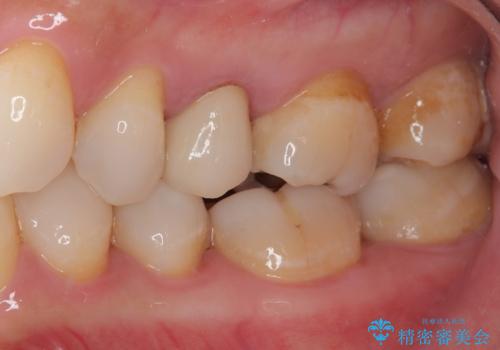

オールセラミッククラウンによる奥歯のむし歯治療

やはりむし歯は大きく、一部歯髄を切除することとなりましたが、その後は良好な経過をたどっています。